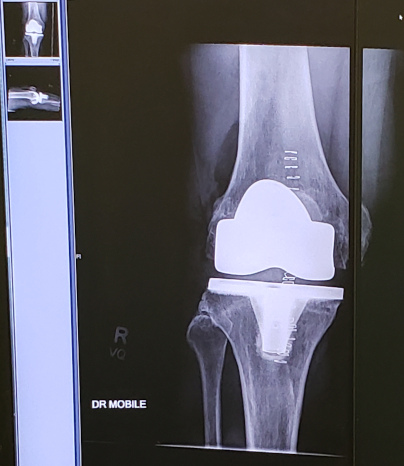

Data Visualization #11—X-rays

If you sit down for a minute and think about it, an x-ray is the culmination of a data generating, and visualization, process. What we see on the screen is a representation (or a model) of the body part being x-rayed. Over a month ago (hence the disruption to my blogging routine) I unexpectedly had knee replacement surgery (yay for cancellation lists!). Here is an x-ray of my new right knee (airport scanners, here I come!):

The parts showing very white are new and will hopefully allow me to hike and bike pain-free from this point on. It’s been a painful, but ultimately productive, healing and rehabilitation process and I’ll be continuing my data visualization challenge beginning next week. See you soon!